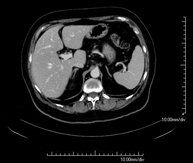

- Abdomen y pelvis- TC Abdomen Prueba diagnóstica que consiste en obtener imágenes del abdomen de alta definición anatómica (hígado, vesícula biliar, vía biliar, páncreas, bazo, estómago, intestinos, riñones, estructuras vasculares, vejiga, útero y ovarios, etc.) mediante el empleo de un equipo de TC (Tomografía Computarizada). Dichas imágenes se estudian posteriormente en una estación de trabajo que permite reconstrucciones bidimensionales en diferentes planos del espacio, y también reconstrucciones 3D (volumétricas). La mayoría de estudios requieren el empleo de contraste yodado para mejorar la definición de las imágenes. Prueba diagnóstica que consiste en obtener imágenes del abdomen de alta definición anatómica (hígado, vesícula biliar, vía biliar, páncreas, bazo, estómago, intestinos, riñones, estructuras vasculares, vejiga, útero y ovarios, etc.) mediante el empleo de un equipo de TC (Tomografía Computarizada). Dichas imágenes se estudian posteriormente en una estación de trabajo que permite reconstrucciones bidimensionales en diferentes planos del espacio, y también reconstrucciones 3D (volumétricas). La mayoría de estudios requieren el empleo de contraste yodado para mejorar la definición de las imágenes.

- TC Abdominopélvico Prueba diagnóstica que consiste en obtener imágenes bi y tridimensionales del abdomen y de la pelvis de alta definición anatómica (estructuras óseas, estructuras vasculares, hígado, páncreas, vesícula biliar, riñones, glándulas suprarrenales, bazo, intestino delgado y grueso, vejiga, útero y ovarios, próstata y vesículas seminales, uréteres, etc.) mediante el empleo de un equipo de TC (Tomografía Computarizada). La mayoría de estudios requieren el empleo de contraste yodado. Prueba diagnóstica que consiste en obtener imágenes bi y tridimensionales del abdomen y de la pelvis de alta definición anatómica (estructuras óseas, estructuras vasculares, hígado, páncreas, vesícula biliar, riñones, glándulas suprarrenales, bazo, intestino delgado y grueso, vejiga, útero y ovarios, próstata y vesículas seminales, uréteres, etc.) mediante el empleo de un equipo de TC (Tomografía Computarizada). La mayoría de estudios requieren el empleo de contraste yodado.

- TC Hígado Prueba diagnóstica que consiste en obtener imágenes bi y tridimensionales del hígado de alta definición anatómica mediante el empleo de un equipo de TC (Tomografía Computarizada). Es necesario realizar el estudio antes y después del empleo de contraste yodado, realizándolo en diferentes "fases hepáticas" para valorar correctamente todas las estructuras: parénquima hepático, vía biliar intra y extrahepática, vesícula biliar, vasos hepáticos (arteria hepática, vena porta y venas suprahepáticas) y estructuras adyacentes (estómago, duodeno, vena cava inferior, glándula pancreática, etc.). Esta prueba está especialmente indicada en el estudio de lesiones hepáticas, el estudio de hepatopatías crónicas, etc. Prueba diagnóstica que consiste en obtener imágenes bi y tridimensionales del hígado de alta definición anatómica mediante el empleo de un equipo de TC (Tomografía Computarizada). Es necesario realizar el estudio antes y después del empleo de contraste yodado, realizándolo en diferentes "fases hepáticas" para valorar correctamente todas las estructuras: parénquima hepático, vía biliar intra y extrahepática, vesícula biliar, vasos hepáticos (arteria hepática, vena porta y venas suprahepáticas) y estructuras adyacentes (estómago, duodeno, vena cava inferior, glándula pancreática, etc.). Esta prueba está especialmente indicada en el estudio de lesiones hepáticas, el estudio de hepatopatías crónicas, etc.